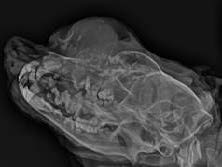

影像学表现为溶骨性膨胀性病变,伴增生性骨膜反应,边缘不规则,骨膜反应呈点状至柱状(图3)。肿瘤起始于鼻孔末端延伸至眼眶区域,与正常骨组织的过渡区界限不清。额骨、鼻骨及上颌骨可见明显破坏,提示为侵袭性骨病变。

图3. X线片示溶骨性膨胀性病变,伴增生性骨膜反应,边缘不规则,骨膜反应呈点状至柱状。

本例报告了一例12岁母犬,其前鼻骨区域出现一巨大组织细胞瘤,直径约10厘米,病程进展迅速。该病例在临床、影像学及病理学上均表现出一定复杂性,尤其在老年犬中较为罕见,增加了诊断难度。初步影像学检查显示该肿瘤伴随明显的骨破坏和骨膜反应,提示为侵袭性病变,因此需与多发性骨髓瘤、骨肉瘤、鳞状细胞癌等恶性肿瘤鉴别。